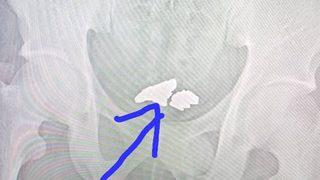

Böyle hırsızlık görülmedi! 81 gram altını yutarak çalmak istedi... Metal dedektörüne yakalandı

Demokratik Kongo Cumhuriyeti'nde altın madeninde çalışan bir adam hırsızlık yapmak istedi ve ilginç bir yönteme başvurdu. 81 gram altını yutan adam kaçmaya çalışırken metal dedektörüne takıldı. Gözaltına alındıktan sonra hastaneye kaldırılan adamın midesinden cerrahi operasyonla 81 gram altın çıkartıldı.